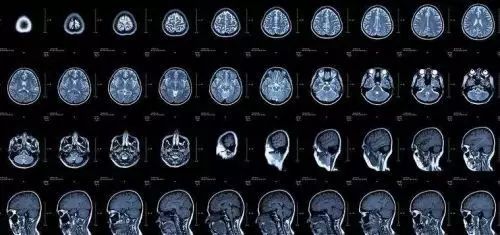

磁共振成像(MRI):摇一摇再看

核磁共振机使用较强大的磁场,使人体中所有水分子磁场的磁力线方向一致,这时磁共振机的磁场突然消失,身体中水分子的磁力线方向,突然恢复到原来随意排列的状态。简单说就相当于用手摇一摇,让水分子振动起来,再平静下来,感受一下里面的振动。根据信号差异,区分不同组织,包括肿瘤组织与正常组织,MRI已应用于全身各系统的成像诊断。效果最佳的是颅脑,及其脊髓、心脏大血管、关节骨骼、软组织及盆腔等。

MRI检查优点

(1)无电离辐射损伤

(2)软组织和解剖结构显示清晰,对中枢神经系统、膀胱、直肠、子宫、阴道、关节、肌肉等检查优于CT

(3)多序列,多方向成像,可配合各种功能成像技术,为明确病变性质提供更丰富的影像信息。

MRI检查缺点

(1)对运动性器官,如胃肠道常常显示不清

(2)对于肺部这类缺少质子的部位检查成像效果不佳。磁共振成像对钙化灶和骨骼病灶的显示,也不如CT准确和敏感

(3)体内留有金属物品者不宜,例如带起搏器及避孕环者。

(4)危重病人不宜

(5)幽闭恐慌症患者不适合检查,检查所需时间较长,运行过程中噪声大